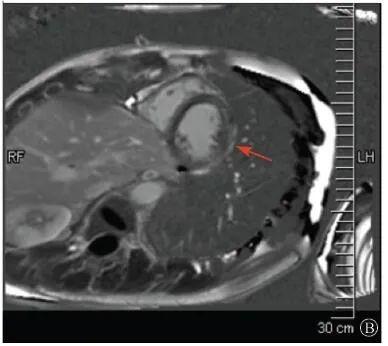

案例介紹:患者男性,20歲,因為"胸痛4個月,加重1月余"于2019年7月10日入院?;颊?019年4月無明顯誘因出現(xiàn)心前區(qū)隱痛,VAS 3分,無放射,無胸悶、憋氣、活動后氣短,每月發(fā)作1~2次,未在意。同年5月體檢發(fā)現(xiàn),肌酸激酶(CK)2928 U/L、肌酸激酶MB質量(CK-MB)46 U/L、心肌肌鈣蛋白I(cTnI)0.055 ng/ml。6月初,患者"感冒"后出現(xiàn)心前區(qū)疼痛加重,為過電樣疼痛,VAS 5分,無放射,持續(xù)約30~60 min可好轉,胸痛每周約發(fā)作2次,否認呼吸困難、胸悶、心悸,否認活動耐量下降。6月8日,患者就診于外院查血生化:CK 1 215→1433 U/L,CK-MB 47 U/L,cTnI 30.17→31.79 ng/L;血脂(-);抗核抗體譜(-);超聲心動圖:左室增大,左室舒張末內(nèi)徑57 mm,左室射血分數(shù)39%,輕度二尖瓣關閉不全;磁共振心肌灌注延遲動態(tài)成像(圖1):左室稍增大,收縮功能稍減低;基底部至心尖部左室下壁及側壁、心尖部左室前壁心外膜下心肌纖維化,考慮非缺血性心肌??;肌電圖:肌源性損害(偏慢性)。診斷"多發(fā)性肌炎、心肌損傷",予患者倍他樂克緩釋片23.75 mg/d、培哚普利0.5 mg/d、螺內(nèi)酯20 mg/d口服,患者未再出現(xiàn)心前區(qū)疼痛,但步行1 km左右會出現(xiàn)氣短、乏力。為進一步明確心力衰竭病因收入我院?;颊呱细咧衅鸪霈F(xiàn)體育課等劇烈活動后雙下肢明顯乏力,不能耐受1 km長跑類運動,日常體力活動不受影響,否認肌肉酸痛等不適。此次發(fā)病以來,一般情況尚可,否認尿量減少,體重無明顯變化。既往史:否認高血壓、冠心病、糖尿病病史。個人史:否認特殊毒物藥物接觸史,無煙酒嗜好?;橛贰⒓易迨罚何椿槲从?,否認家族類似病史,否認遺傳病史。入院查體:脈搏69次/min,血壓112/70 mmHg,指氧(自然狀態(tài))98%,體質指數(shù)21.1 kg/m2;無皮疹;雙肺呼吸音清;心律齊,未聞及雜音;肝脾不大;雙側腓腸肌肥大,肌肉無壓痛;四肢肌力Ⅴ級、肌張力正常。雙下肢不腫。輔助檢查:入室床旁超聲心動圖提示左室壁運動普遍減低,心尖部、左室下后壁為著,肌小梁增多。

左室壁較廣泛心外膜下延遲強化,可見左室下后壁肌小梁增多(箭頭所示)

圖1 患者外院磁共振心肌灌注延遲動態(tài)成像